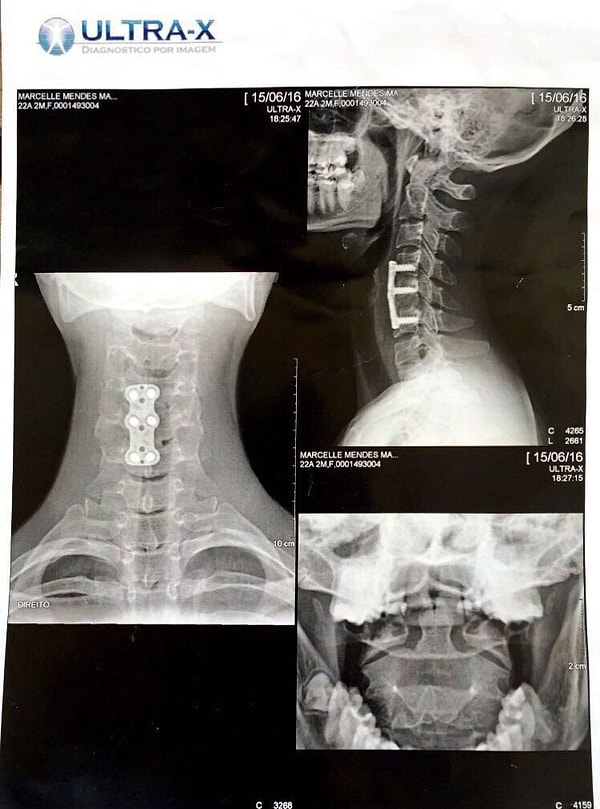

Марселле соскользнула с тренажера, выполняя упражнение на пресс, и сломала позвоночник. Врачи сказали, что она может быть парализована на всю жизнь. Они установили титановую пластину, удерживаемую шестью винтами, в позвоночник молодой женщины.